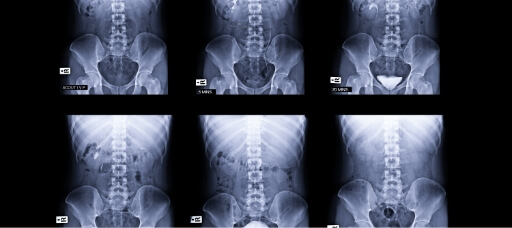

- Diagnóstico preciso con estudios de imagen avanzados

TESTING

Normalmente es necesario hacer test para poder obtener un diagnóstico preciso y acertado. Tenemos acceso a tecnología de imagen digital para visualizar el riñón.